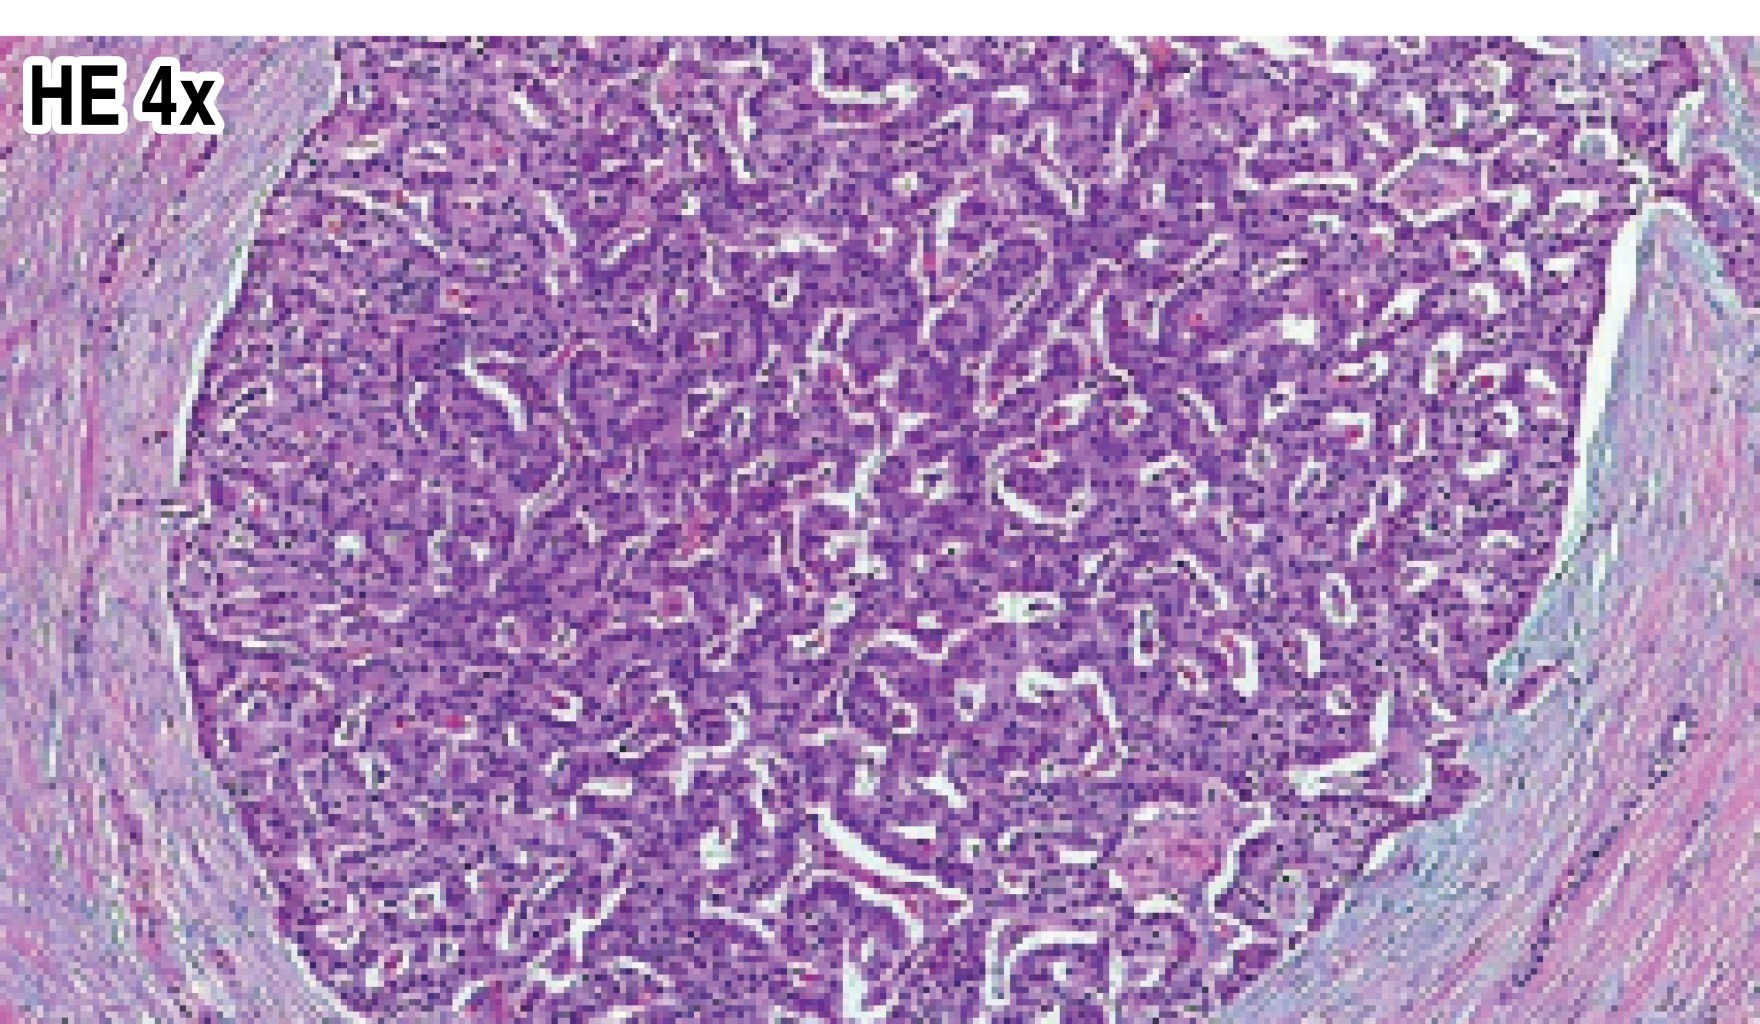

On multiple occasions, he required attention in the emergency department where the presence of hypoglycemia was evidenced and treated with a glucose solution that improved the clinical picture. In general, the physical examination was normal. His weight was 90 kg, height 170 cm, and body mass index (BMI) was 31.1. As part of the diagnostic approach, a fasting test was performed, which had to be suspended after 18 hours due to neuroglycopenic symptoms. Serum hyperinsulinism was identified with serum glucose of 56 mg/dl, serum insulin of 79 μU/ml, C-peptide of 10.2 ng/ml, and an insulin/glucose ratio of 13.1. A three-phase helical computed tomography scan was taken which showed a round nodule, with well-defined contours, solid, of superficial location in the distal portion of the tail of the pancreas measuring 12.9 mm in diameter, hypodense in the arterial phase and hyperdense in the portal phases, mainly in the venous phase. The radiological report was of suspicion for insulinoma (Figure 1). Based on the findings of the imaging studies, the patient was scheduled for a laparoscopic distal pancreatectomy, which was performed without complications. The histopathological study reported a 3.5 × 3 × 2.5 cm, pinkish-yellow, single, spherical lesion with a purplish-gray surface measuring 1.5 × 0.9 × 0.9 cm. Pancreatic islet hyperplasia and isolated endocrine cells were seen, as well as an accessory spleen in the tail of the pancreas. Immunohistochemistry revealed positivity for synaptophysin and chromogranin in the pancreatic islets of Langerhans with a ki67 proliferation index of 1%. With all these data, diffuse nesidioblastosis was diagnosed (Figures 2 and 3). The patient's follow-up has shown adequate glycemic control and remission of neuroglycopenic events until this time.

The definitive diagnosis is made by histopathology means, using neuroendocrine markers, and observing whether the histologic criteria (major and minor) for the diagnosis of nesidioblastosis are met.9 Treatment with drugs such as glucocorticoids, somatostatin analogs or diazoxide can be initiated to control insulin secretion; however, if there is a persistence of symptoms, the treatment of choice is surgical resection. In most cases distal pancreatectomy is performed; if the symptoms do not remit after the intervention, the previously mentioned drugs can be used as a complementary treatment.10